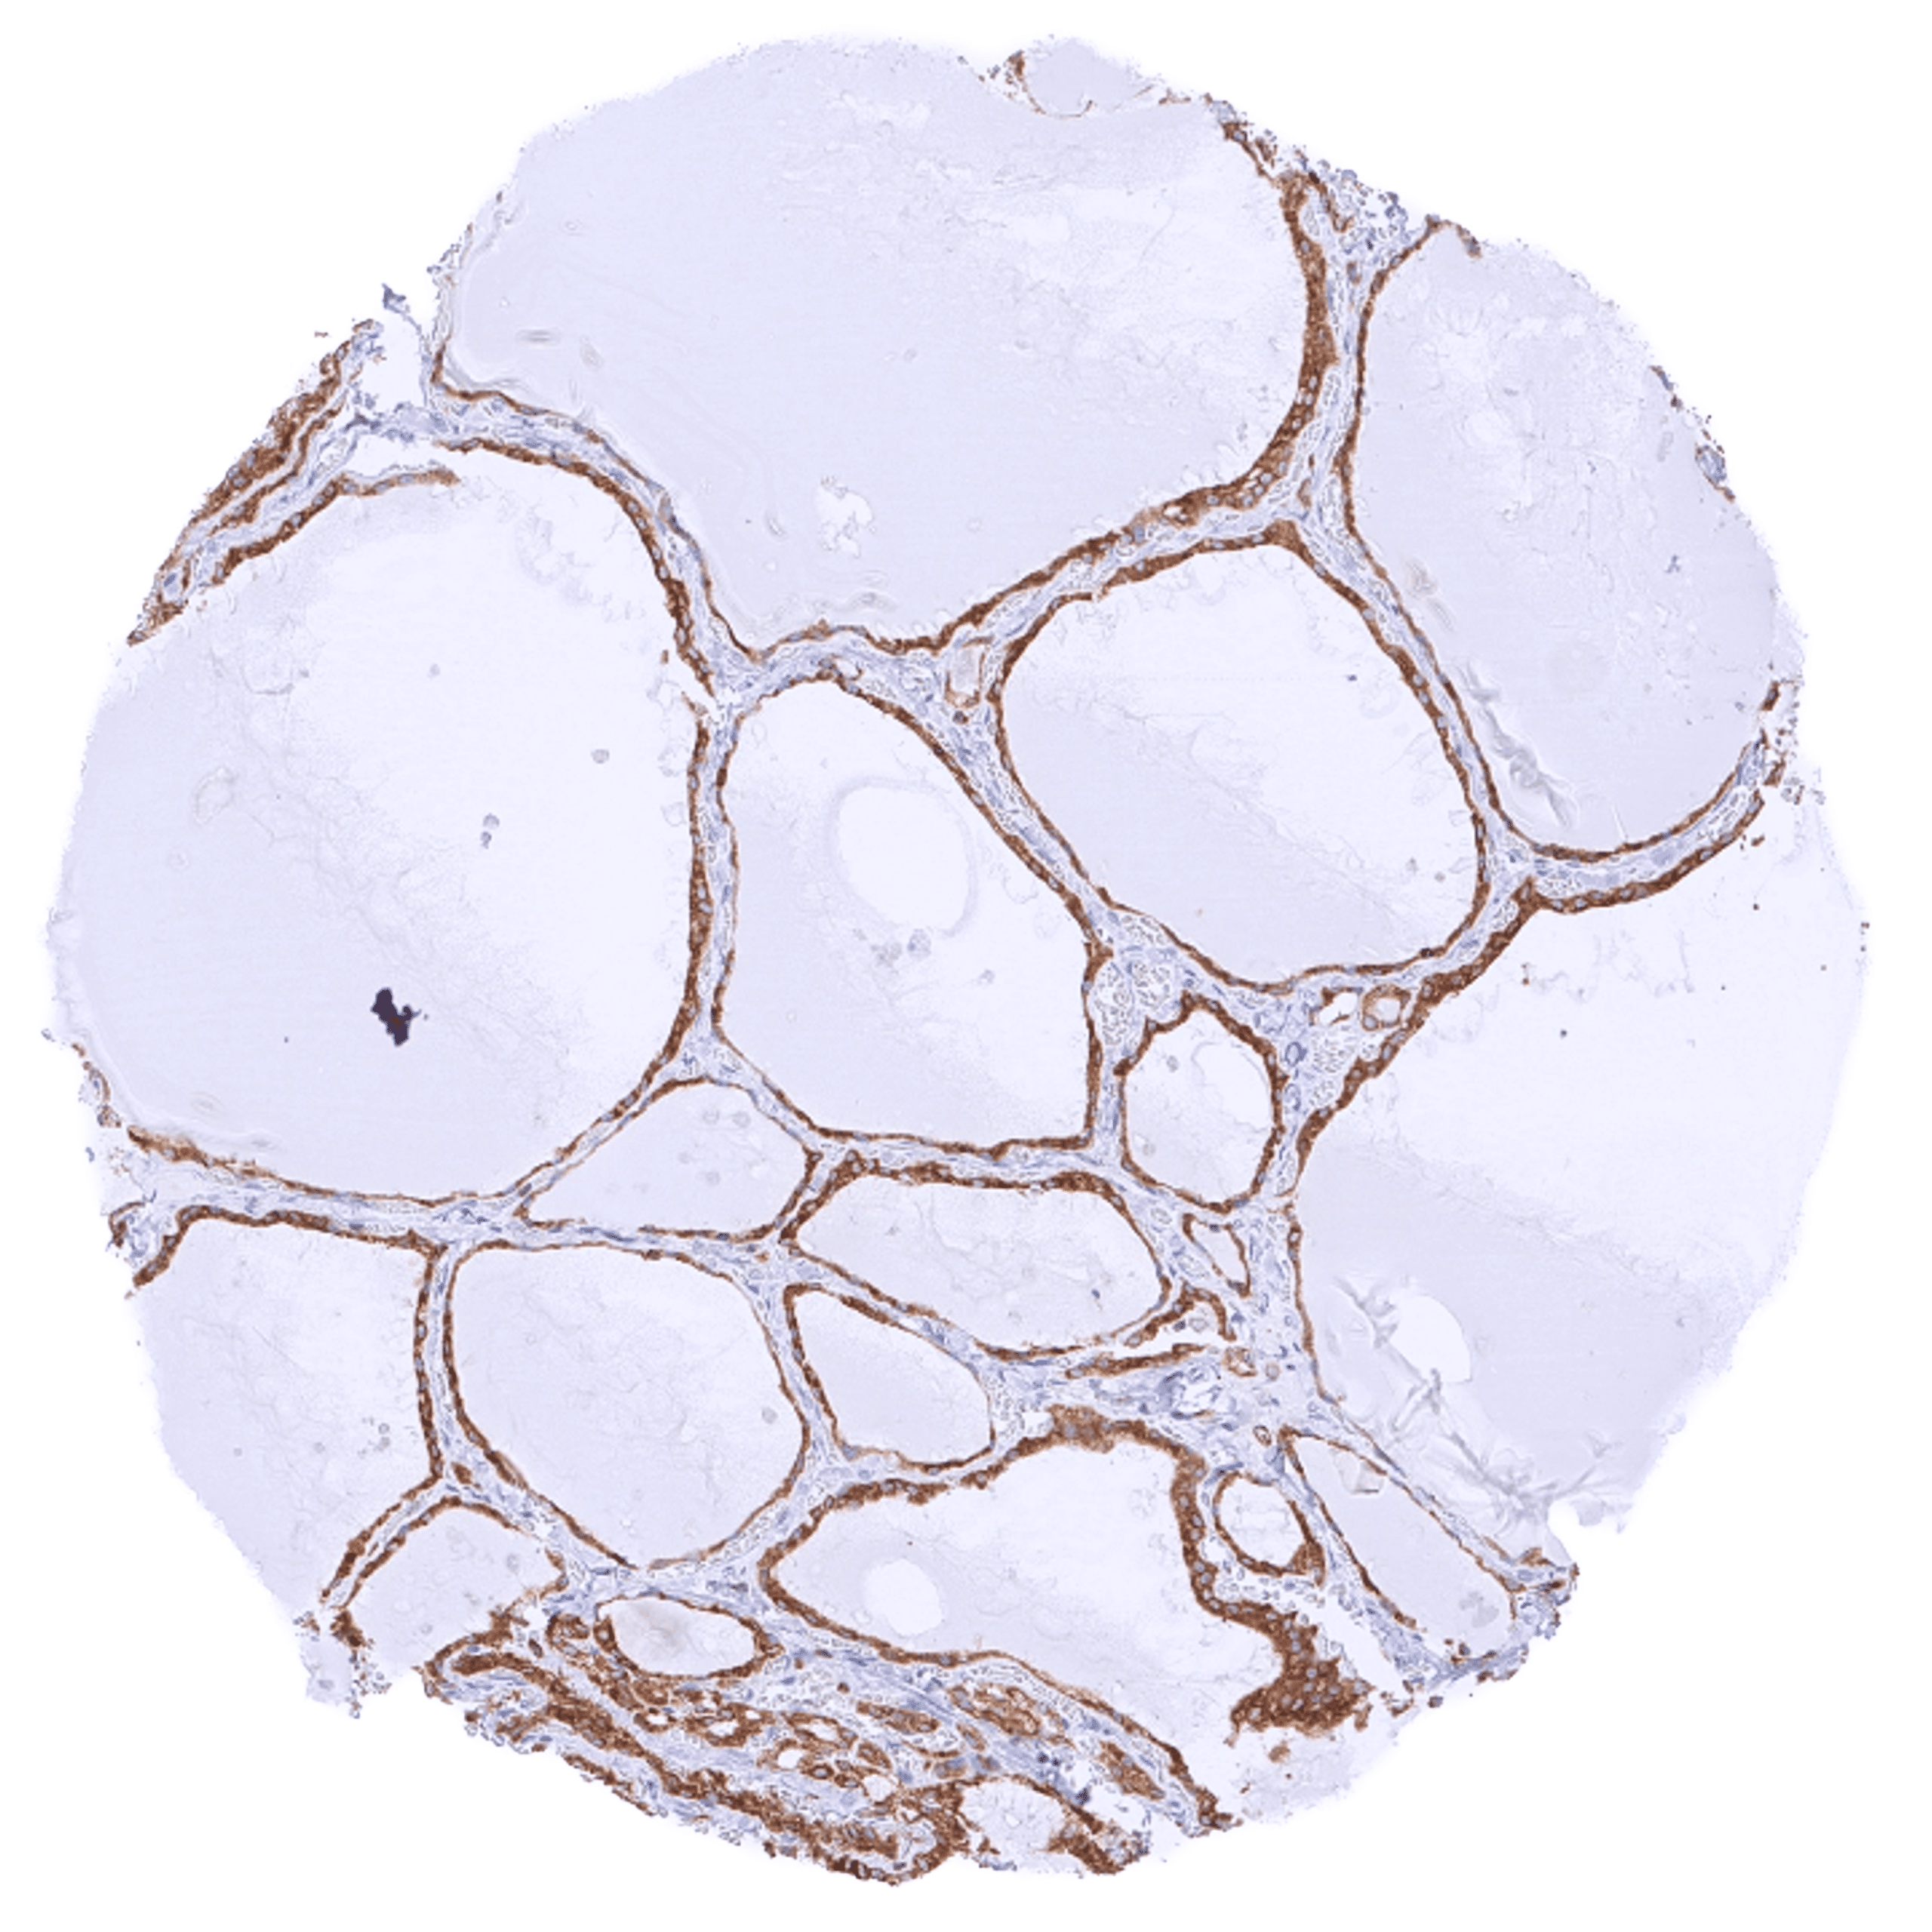

| Endocrine Tissues | Thyroid | Strong cytoplasmic bcl-2 staining of follicular cells. |